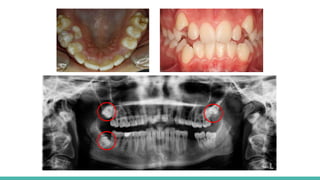

DIENTES IMPACTADOS

Diente totalmente impactado

Diente parcialmente impactado

COMPLICACIONES

TRATAMIENTOS

● Reabsorción de la raíz

● Infección y dolor asociado.

● Quistes dentígeros

● Reabsorción externa del diente impactado.

● Exodoncia.

● Ortodoncia.

DIENTES IMPACTADOS Diente totalmenteimpactado Diente parcialmente impactado COMPLICACIONES TRATAMIENTOS ● Reabsorción de la raíz ● Infección y dolor asociado. ● Quistes dentígeros ● Reabsorción externa del diente impactado. ● Exodoncia. ● Ortodoncia.

• #15 Aunque virtualmente cualquier diente puede estar impactado, los dientes impactados más frecuentes son los terceros molares superiores e inferiores. Los terceros molares se clasifican según su orientación dentro de la arcada. (impactaciones mesioagunlar, distoangular, horizontal y vertical.

• #16 Un diente impactado que está rodeado totalmente por hueso se considera como totalmente impactado, mientras que uno situado parcialmente en el hueso y parcialmente en tejido blando se considera como parcialmente impactado. Los dientes parcialmente impactados, en especial los terceros molares inferiores, pueden comunicarse con la cavidad oral por medio de una bolsa periodontal apenas perceptible situada sobre la cara disal del segundo molar contiguo, predisponiendo así al diente impactado a infección pericoronal y caries dental. Un diente que está totalmente impactado no se comunica con la cavidad oral y por tanto no es vulnerable a infección. COMPLICACIONES: 1. Reabsorción de la raíz de los dientes normales adyacentes, infección y dolor asociado, predisposición a la formación de quistes dentígeros y la reabsorción externa del diente impactado. La reabsorción externa de un diente impactado suele iniciarse en el área oclusal de la corona y se parece radiograficamente a la caries dental. TTO: los tto variará según el diente afectado y las circunstancias individuales. La mayoria se extraen quirurgicamente. Los caninos son un pilar fundamental en cuanto a la guía y dentición, por ello suelen hacerse esfuerzos especiales para su conservación